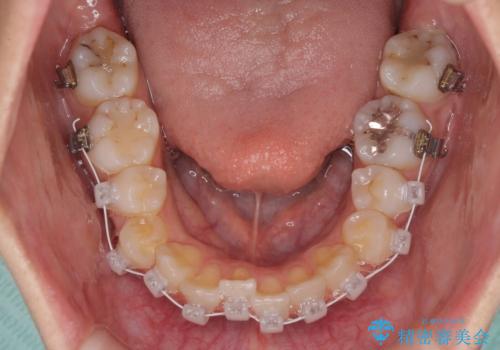

急速拡大装置を用いて上顎骨を側方に拡大し、上顎の叢生を解消するとともに下顎歯列拡大により下顎の叢生も解消することとしました。

急速拡大装置使用直後は著しいスペースが正中に発現するため、ワイヤー矯正を行いますが、今回は治療期間を短くしたいとのことで、上下全体をワイヤー装置にて矯正治療することとしました。